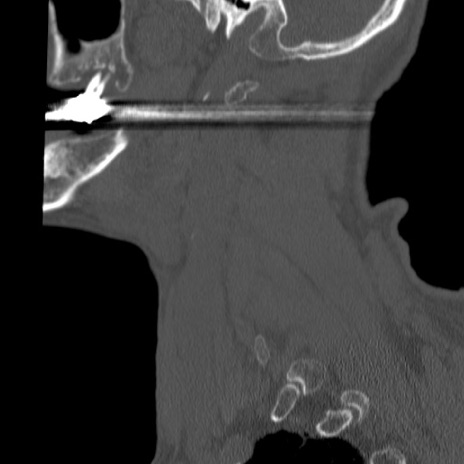

症例46 頚椎CT(矢状断像)

【症例】80歳代男性

【主訴】両側頚部〜上肢のしびれ

【現病歴】昨日、自宅内で転倒、その後より上記症状あり。意識障害なし。

【身体所見】両側上肢のallodynia(熱痛覚過敏)あり。MMTおよびDTRは正確な所見取れず。両上肢の挙上はなんとか可能。

異常所見と診断は?